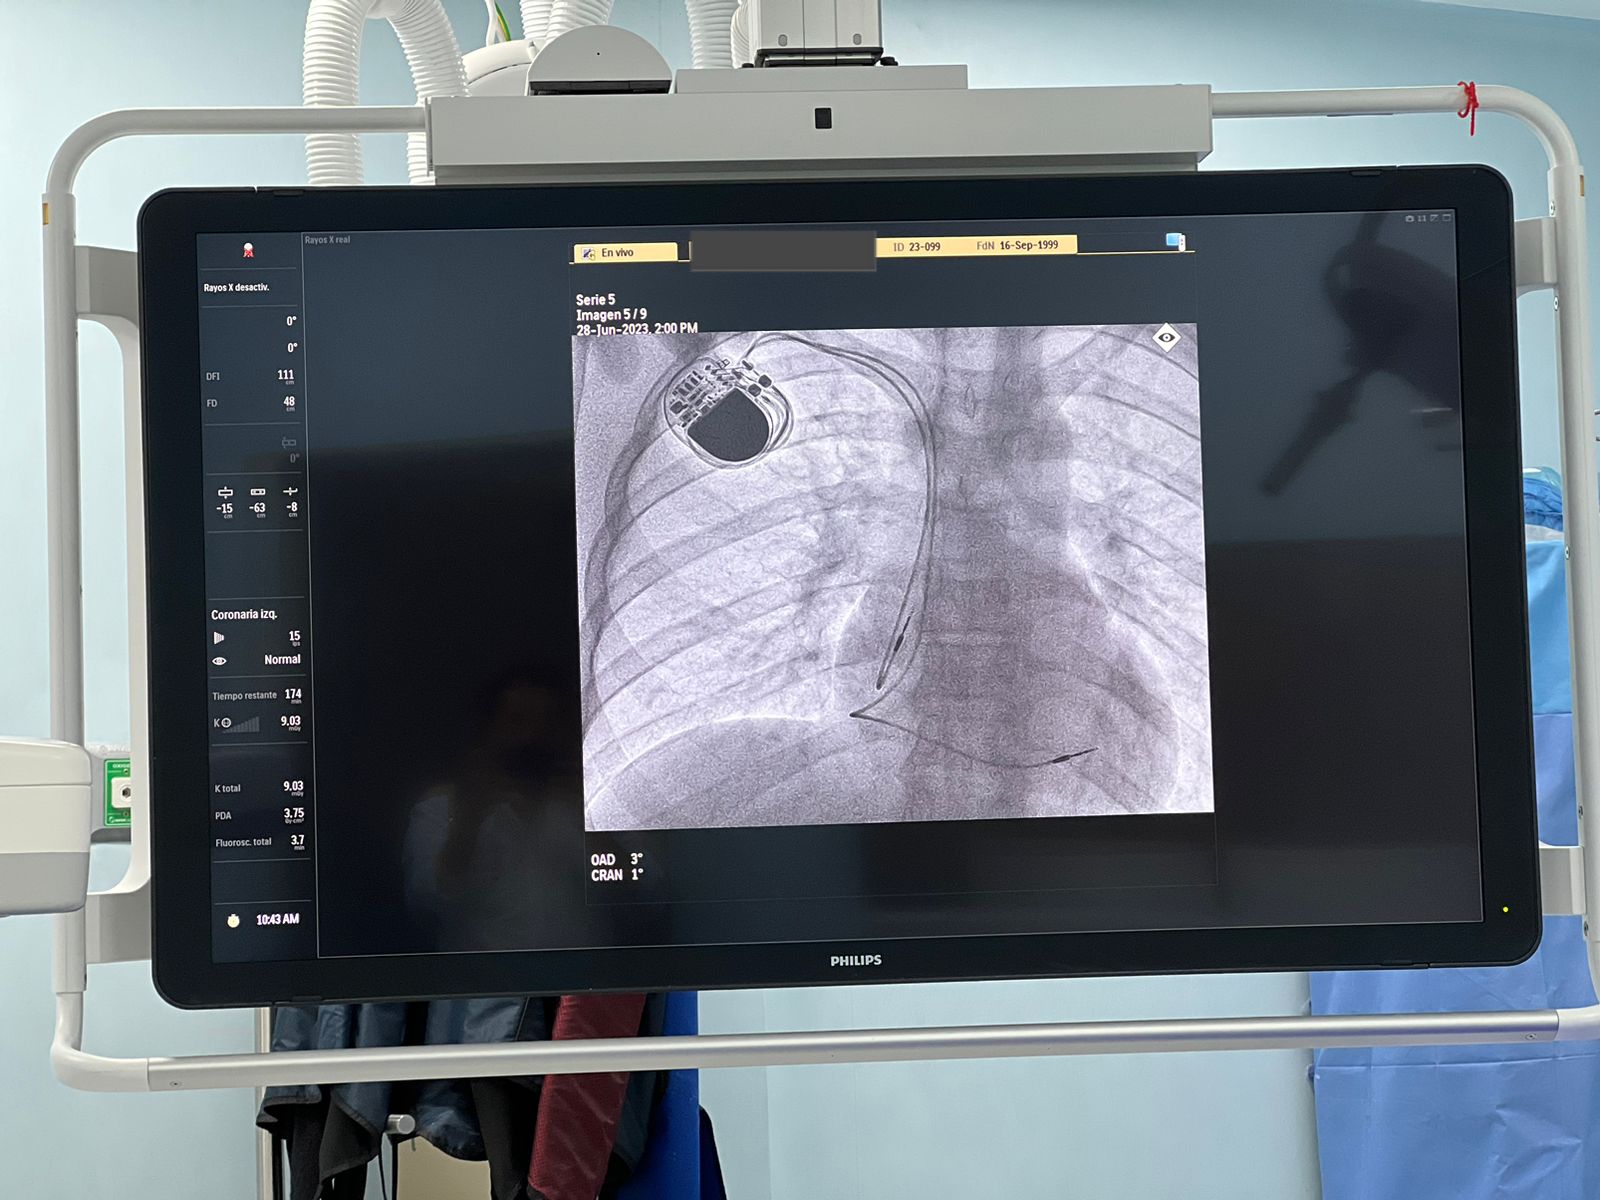

Actualmente la medicina ha avanzado y existen mecanismos y tratamientos para prolongar y mejorar la calidad de vida de pacientes con insuficiencia cardiaca, “es muy importante saber que hay dispositivos implantables que tienen una repercusión positiva en el paciente denominada TRC (Terapia de Resincronización Cardíaca), que, a través de señales eléctricas enviadas al corazón, ayuda a que los ventrículos y aurículas trabajen de manera coordinada, regulando el bombeo cardíaco, por lo que suele utilizarse para tratar arritmias, es decir ritmos cardíacos rápidos, irregulares o lentos”,

Señaló que existen dos tipos de TRC y si bien, ambos envían señales de manera continua para que el corazón pueda bombear con normalidad, la diferencia entre estos dispositivos consiste en que uno de ellos, el TRC-D, incluye un Desfibrilador Automático Implantable (DAI), de modo que, al monitorear el corazón y detectar que se detiene, puede enviar una descarga eléctrica para reanimarlo, solo en caso de ser necesario, ayudando a corregir arritmias mortales.

Todos los dispositivos TRC cuentan con tres cables, conocidos como electrodos, que son conectados de forma particular; el primero dentro de la aurícula derecha, el segundo dentro del ventrículo derecho y el tercero dentro de una vena en la parte exterior del ventrículo izquierdo. ¿Cuáles son los tamaños de desfibriladores?, “en lo referente a sus dimensiones, ambos son dispositivos muy pequeños, el TRC-P mide 5.9 centímetros y pesa 26 gramos; mientras que el TRC-D mide 5.1 centímetros y pesa 80 gramos”, explicó